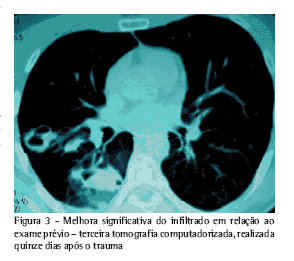

Foi iniciado esquema antibiótico (amoxacilina + ácido clavulânico e ciprofloxacina) após coleta de culturas de sangue, urina e escarro. As culturas de urina e sangue foram negativas. No escarro houve crescimento de Streptococcus b hemolítico. O paciente obteve alta hospitalar após quinze dias de internação, já com melhora clínica e normalização dos exames laboratoriais. A tomografia computadorizada de tórax realizada no dia da alta, evidenciou melhora significativa em relação aos achados do exame anterior (Figura 3).